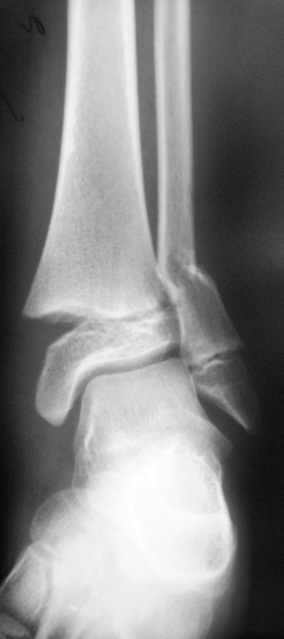

Пациент лечится в "другом лечебном учреждении", но снимки делает "по месту жительства", по направлению лечащего врача.

Мнения, как это довольно часто бывает, "разошлись". Хотелось - бы услышать Ваше мнение, как специалиста травматолога и мнения коллег по:

- процессу консолидации;

- удовлетворительности (неудовлетворительности) сопоставления костных отломков.

Продольная ось костьи нарушена, однако диастаз отломков незначительный, консолидация не выражена, но срастется обязательно, если не будет вторичного смещения.

Уважаемый OPEXOB прав, в данном случае имеет место вторичное смещение отломков, фиксация отломков проведенная этой методикой неадекватная. Видно, в какой то момент было захождение дистального отломка по длине, почему это произошло это уже момент случая, впринципе признаки консолидации умеренно выражены. Вот только одно Валентин Львович смущает есть критерии рентген-контроля которые указываются травматологом с целью отценки признаков консолидации и исключения вторичного смещения, этот случай видимо исключение.

Кстати уважаемый OPEXOB почему вас смутила данная методика, она вам известна, обычно фиксируют L- или Т- образными пластинами с винтами, просто в этом случае это более дешевле, т.е. с экономили.

На каком уровне ЦРБ/ГБ? Для ЦРБ может и сойти, для ГБ - сомнительно, такие переломы надо спец. пластинами с шурупами фиксировать. В общем не люкс, но результат можно считать приемлемым: стояние отломков удовлетворительное (небольшое захождение), формируется костная мозоль. Для полного счастья не хватает бокового снимка (хотя бы через грудную клетку, можно попытаться кассету под мышку засунуть, дополнительно луч скосить - перелом достаточно "низкий").

Методика остеосинтеза действительно не "общеупотребительна". Есть методика остеосинтеза проксимальных переломов плеча спицами, но там спицы несколько другие. Однако, как говорят, победителей не судят - стояние отломков для данного перелома вполне допустимое. Костная мозоль есть, перелом срастается. Всё должно быть хорошо.